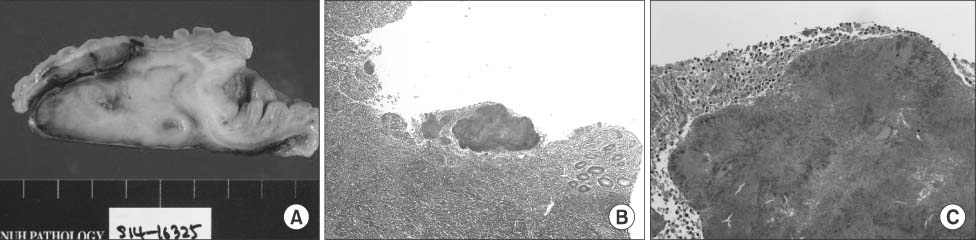

Gross pathology revealed severe inflammation and adhesion between the appendix and the adjacent appendiceal serosal surface. Irregular nodularity was seen in the distal portion of the ileal mucosal area, while intraluminal obliteration was found due to the severe inflammation (Fig. 3A).

Light microscopic examination revealed acute suppurative appendicitis with a periappendiceal abscess and actinomycotic colonies. At higher magnification, a typical sulfur granule surrounded by neutrophils was found that was confirmed as appendiceal actinomycosis (Fig. 3B, C).

Fig. 3

(A) Gross appearance of the excised specimen. (B) Pathological examination: Presence of Actinomyces israelii. Acute suppurative appendicitis with a periappendiceal abscess and actinomycotic colonies characterized by sulfur granules (H&E stain, ×40). (C) Pathological examination: Presence of A. israelii. Acute suppurative appendicitis with a periappendiceal abscess and actinomycotic colonies characterized by sulfur granules (H&E stain, ×200).

Fig. 3 (A) Gross appearance of the excised specimen. (B) Pathological examination: Presence of Actinomyces israelii. Acute suppurative appendicitis with a periappendiceal abscess and actinomycotic colonies characterized by sulfur granules (H&E stain, ×40). (C) Pathological examination: Presence of A. israelii. Acute suppurative appendicitis with a periappendiceal abscess and actinomycotic colonies characterized by sulfur granules (H&E stain, ×200).